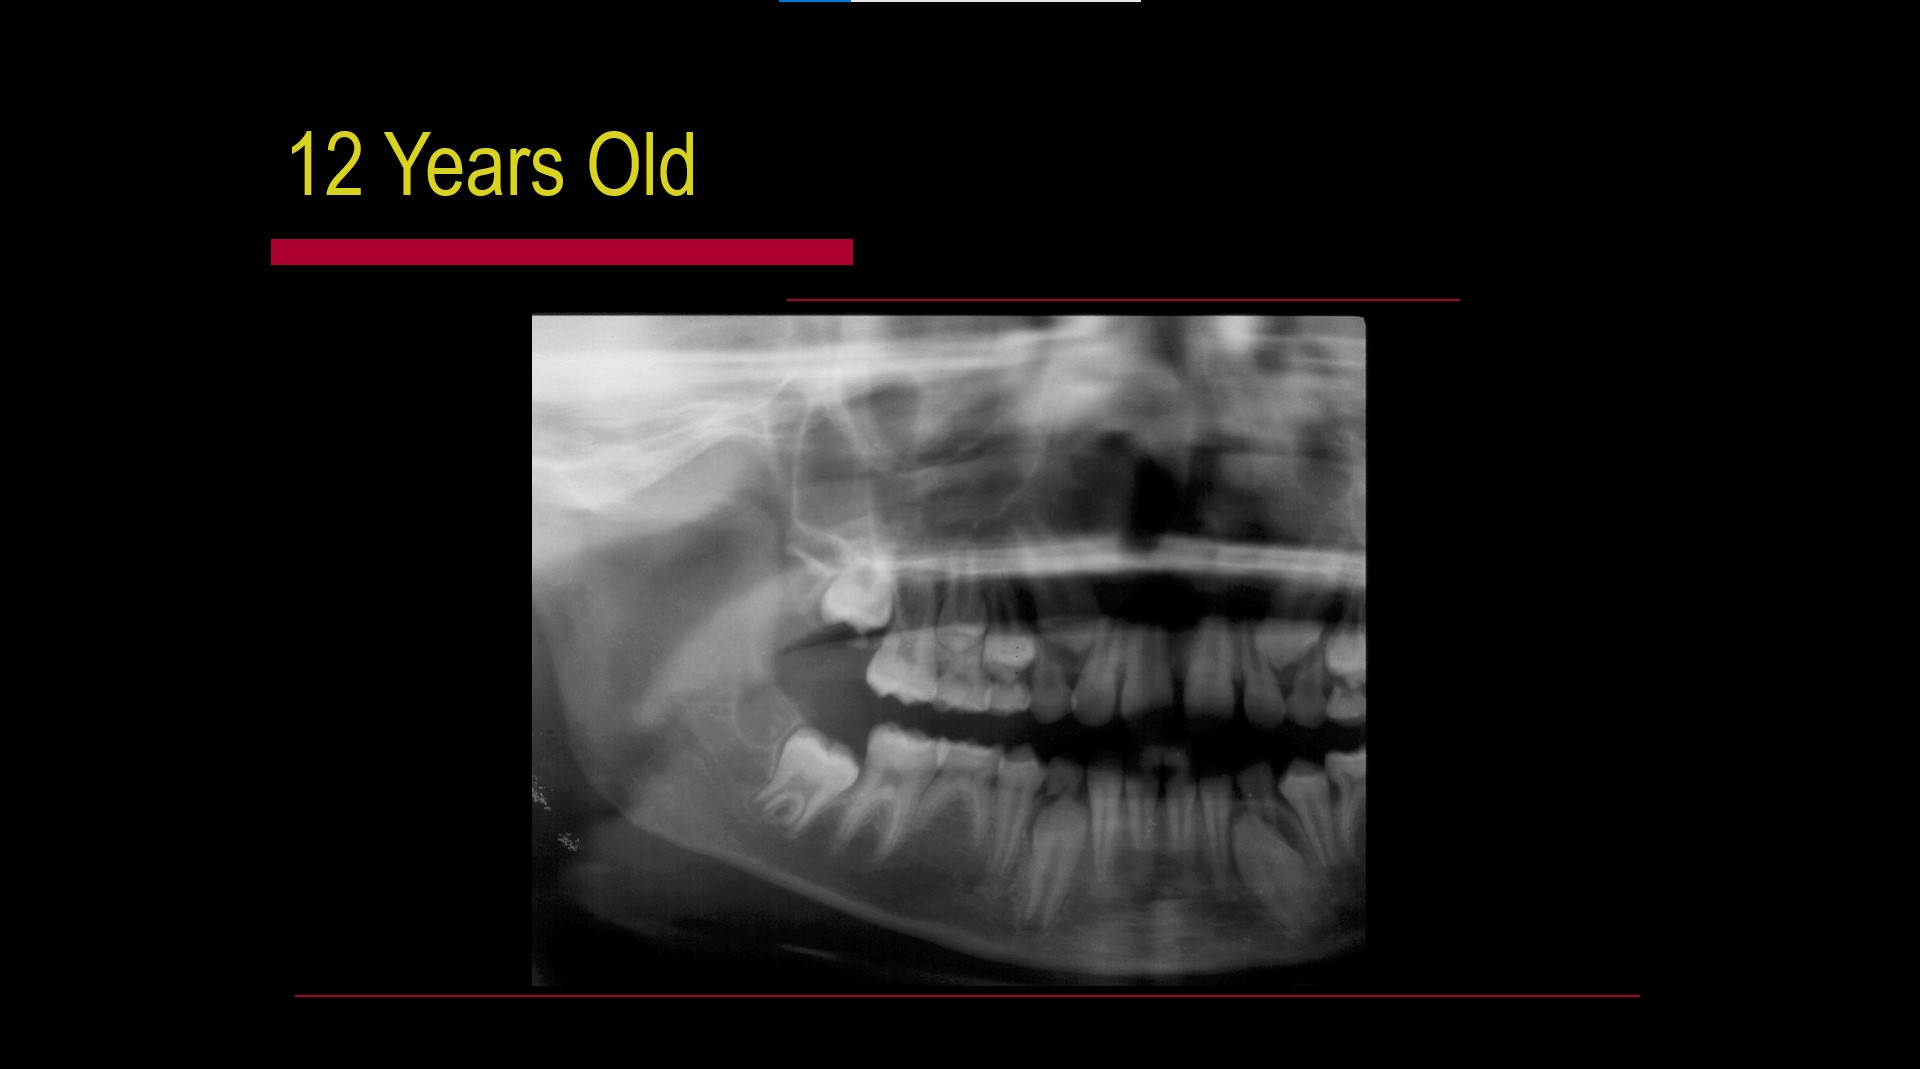

Impacted teeth

Pericoronitis